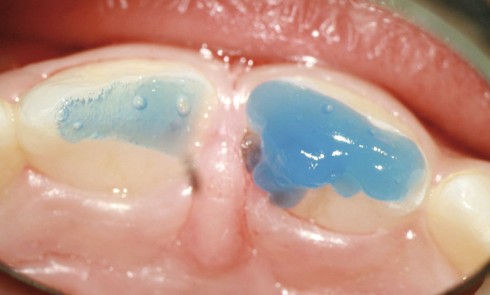

Article réservé à nos abonnés Les systèmes adhésifs MR3 (Mordançage-Rinçage en 3 temps)

Matériel Seringue de gel d’acide orthophosphorique à 37 %Flacon de primer Flacon d’adhésif 2 microbrossesLampe à photopolymériser (> 600 mW/cm2)

Article réservé à nos abonnés Les systèmes adhésifs MR2 (Mordançage-Rinçage en 2 temps)

Matériel Seringue de gel d’acide orthophosphorique à 37 %Flacon (primer + adhésif)1 microbrosseChlorhexidine à 0,2 % et godetLampe à photopolymériser (> 600...